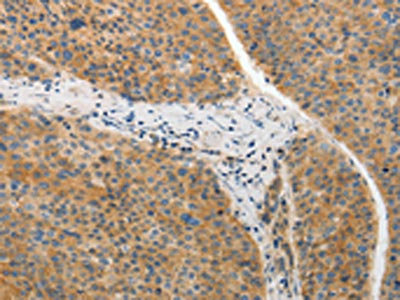

The image on the left is immunohistochemistry of paraffin-embedded Human liver cancer tissue using CSB-PA141929(ADIPOR2 Antibody) at dilution 1/20, on the right is treated with synthetic peptide. (Original magnification: ×200)

The image on the left is immunohistochemistry of paraffin-embedded Human lung cancer tissue using CSB-PA141929(ADIPOR2 Antibody) at dilution 1/20, on the right is treated with synthetic peptide. (Original magnification: ×200)